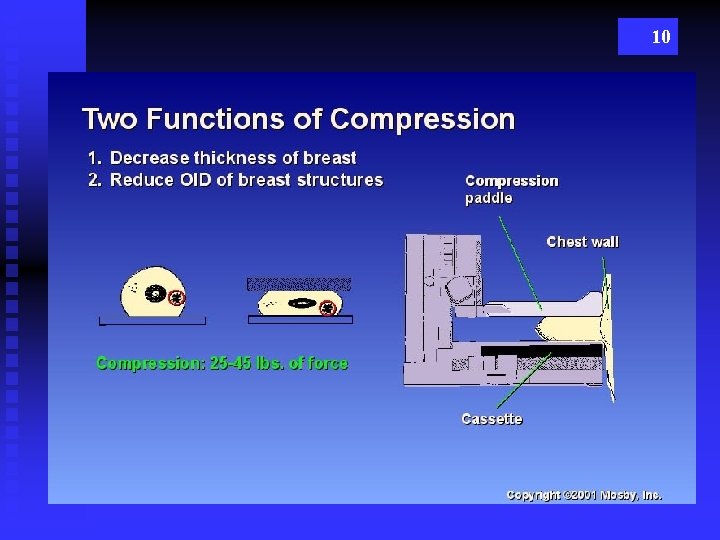

10

14 Compression Important: Evens Density of Breast Reduces Motion AEC choice depends of size and composition of breast